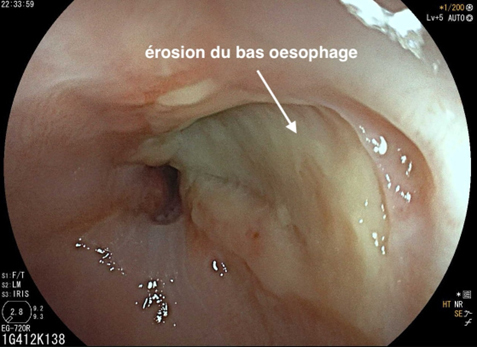

Depuis un an, elle rapporte des crampes d’estomac, notamment après des repas copieux, évoluant par périodes, ainsi qu’un pyrosis nocturne plusieurs fois par semaine. Elle a remarqué dernièrement une gêne thoracique lorsqu’elle boit de l’alcool et lors de ses séances de sport. Il n’y a pas de troubles du transit.

Le pyrosis et le syndrome postural sont des signes typiques de RGO.